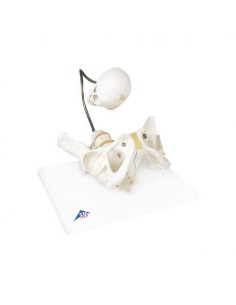

3B Bassin scientifique, anatomique Modèle pour illustrer l'accouchement L30